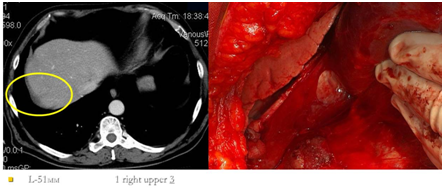

Figure 5 Implants of abdominal surface of the right diaphragm on CT scan and intraoperative image.

Figure 6 Implants of liver fibrous capsule (Glisson's capsule) on CT scan and intraoperative image.